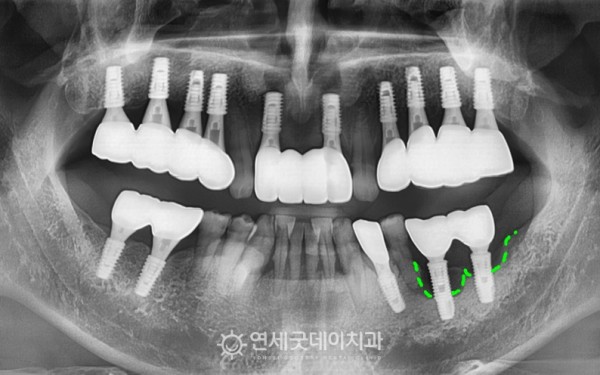

치근단염이 관찰되었던 #35 부위 발치와

타원 임플란트를 안정적으로 제거하였으며

제거 후에는 추후 새로운 임플란트를 안전하게 심고

두툼한 잇몸뼈 기반을 만들어주기 위해

뼈이식을 진행했습니다

환자분은 흡연 조절이 어려우셔서

치료 과정이 쉽진 않았지만

그럼에도 잇몸뼈가 다시 자리잡고,

임플란트가 안정적으로 식립된 모습입니다.

치료전과 후를 보시면 완전히 내려 앉았던 잇몸뼈가

최대한 두툼하게 재생되며 잘 회복된 모습입니다.